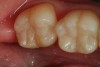

Figure 3. An occlusal view of tooth numbers 18 and 19 after anatomic placement of the enamel “capping” layer (Xtra-Fil: VOCO America), finishing, and polishing.

Figure 3

Because of their transparent nature, and decreased percentage of filler particles, bulk fill flowable composites require a conventional nanohybrid composite material to be placed as the “enamel-capping layer” (Figure 3).13-15